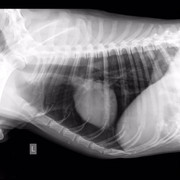

Нас 6-ро, и все они замечательные ребята с большим сердцем. Эта ситуация личная для меня, и я всеми силами хочу сделать добро, вылечить животное, которое я собственноручно вытягивала с проезжей части, которого гладила, пока ему ставили капельницу и измеряли давление врачи круглосуточной ветклиники. Спокойный умный пёс, который оказался на улице по вине человека. Он не щенок, он в самом расцвете, думаю, но такой добрый, отзывчивый и спокойный, и борющийся за жизнь. У собакена перелом таза, сильные ссадины, осколки таза навредили внутренним органам и нужна операция, последующее дорогостоящее и долгое восстановление. Также есть вопросы по дерматологии, пёсель уличный - завтра врачи возьмут соскоб, чтобы попытаться восстановить волосяной покров животного.

Собаке сделали операцию, но не на тазу (таз вправили ректально), а на передней лапе, которая оказалась сломана, но в виду того, что собака была лежачей и болезненно реагировала на перемещения по клинике, про перелом выяснилось позже. Поставили спицы.

У него есть чувствительность задних лап, поэтому проводимость есть. В туалет пошел сам. Врачи говорят операция на тазу не нужна.

Цитата Саша (  )  говорят операция на тазу не нужна.У него перелом таза, что гораздо серьезнее его сломанной и прооперированной лапы. У него же таз перекошен и лучше вряд ли при постоянном движении будет. Снимки таза и пса самого осматривал опытный травматолог?

Ну дело, конечно, хозяйское, или кураторское точнее, но я бы поинтересовалась, какой прогноз лечащий врач даёт при консервативном лечении (вернее нелечении) сломанного таза и когда планируется контроль сращения. Потому что при постоянной подвижности костей в месте перелома таза есть угроза того, что пёс станет инвалидом. При правильном лечении и фиксации - выздоровеет полностью. Здесь ведь на форуме небезразличные люди собрались и советы дают из своего волонтерского опыта (вам советовали везти пса к проверенным опытом травматологам, пч все ветеринары - специалисты широкого профиля, и лишь единицы являются узкими и грамотными специалистами в определённой области, в травматологии в частности, чему учатся годами). Вашему подопечному все желают только скорейшего выздоровления, поэтому и пишут здесь

меня зовут Алена и я одна из очевидцев и посетителей Собакена. спасибо большое, за ваше внимание к нашей истории и за желание помочь!!на данный момент его снимки смотрели в САСе, а также лечащий врач моего кота (Мурыченков Евгений - отличный врач, много раз возвращал моего Зефира с того света). оба врача сейчас подтвердили что таз оперировать нет необходимости, как нам объяснили процесс заживления будет в обоих случаях аналогичный (шуруп Собакен может вырвать случайно, при постановке шурупа этого возможно повредить нервы). чувствительность ног у него в порядке. соскоб на клеща делали, но его не нашли, возможно это нарушение функции надпочечников. но нам порекомендовали полечиться от клеща после того как у него восстановится печень (сейчас множественные ушибы внутренних органов)